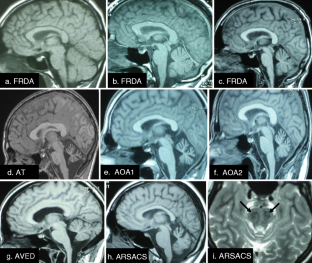

Fig. 1